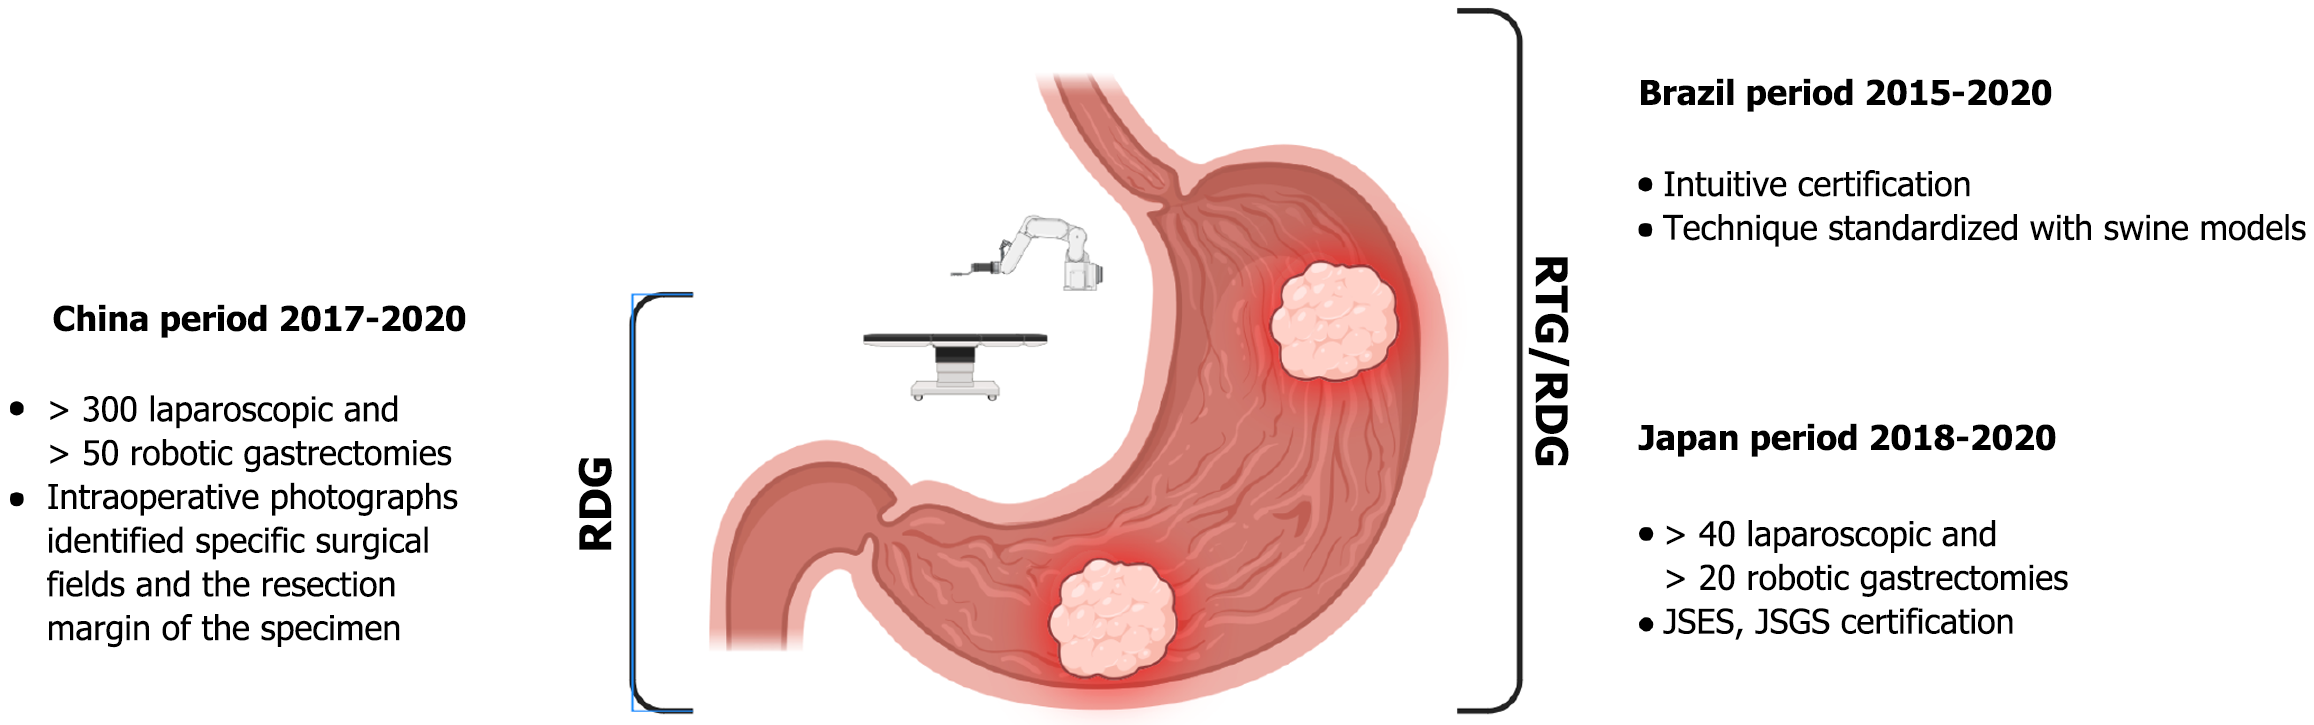

Anastomotic leakage is the Achille’s heel of the surgeon. Many predictive factors have been identified: Patient-related (preoperative nutritional status, smoking, respiratory and cardiological pathologies), tumor-related (mixed-type histology), and operative variables, D2 or more lymphadenectomy, laparoscopic approach (15.1% vs 7.7% in open gastrectomy), multivisceral resection and reconstruction technique, with circular anastomosis at high risk of developing leakage[62,63]. The impact of surgeon experience has also been documented as an independent risk factor for leakage, ranging from 12% for less experienced surgeons (< 30 gastrectomies) to 2.2% for highly experienced surgeons[64]. Although the introduction of laparoscopy initially limited the use of hand sewing due to its technical requirements, the greater flexibility of robotic systems has made hand sewn esophagojejunostomy easier and more feasible (leakage in 1 out of 54 cases)[65]. The incidence of postoperative leakage tends to decrease after the first 15 cases, reflecting the robotic learning curve for gastrectomy[66]. Similar advantages have been described with the Albert-Lembert with knotless barbed sutures method for esophagojejunostomy during robotic assisted total gastrectomy (1 of 31 cases), with no occurrence of anastomotic stenosis, and the intracorporeal phi-shaped esophagojejunostomy (1 of 11 cases)[67,68]. The Upper Gastrointestinal International Robotic Association registry reported anastomotic leak rates of 10% (4.5% circular stapled, 3.4% hand sewn, 2.1% linear stapled) and 2% (all linear stapled) after robotic assisted total gastrectomy and RADG, respectively. Robotic linear staplers also appear to be associated with fewer anastomotic strictures than circular staplers due to easier calibration of the anastomotic angle and more precise reinforcement of the anastomosis[69]. With the aim of overcoming surgeon-related bias in demonstrating non-inferiority of robotic gastrectomy, completed trials have defined precise inclusion criteria for participants (Figure 3).